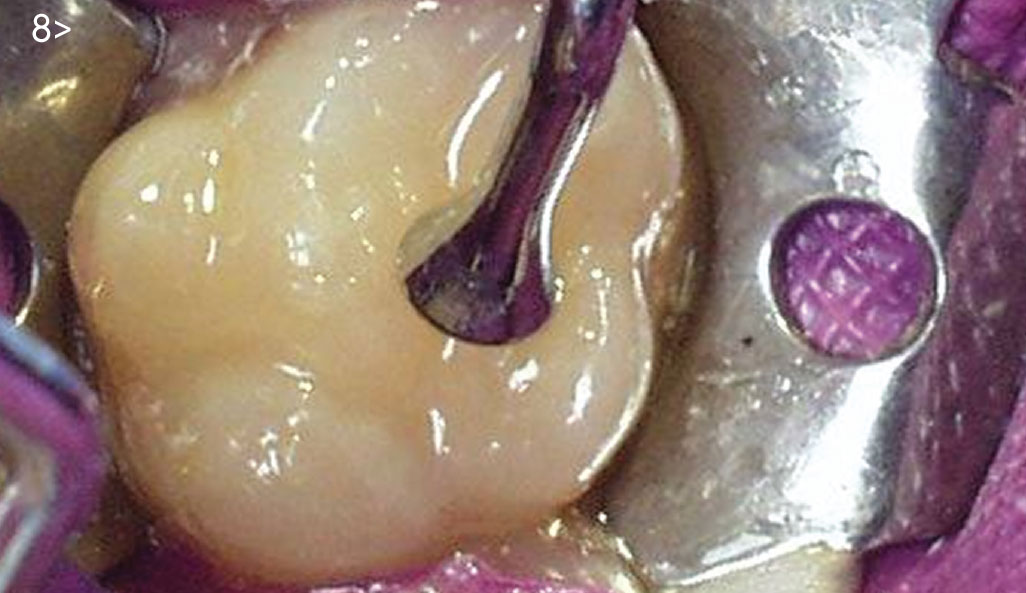

- Fig. 7: Phosphoric acid etching the enamel and remaining dentin.

- Fig. 8: Resin-based composite being incrementally placed on top of the direct pulp cap.

was then light cured with a LED curing light for 20 seconds. An adhesive

using the total-etch technique was placed on top of the pulp

cap and the surrounding dentin (Fig. 7). A conventional resin-based

composite was incrementally placed, finished and polished (Fig. 8).